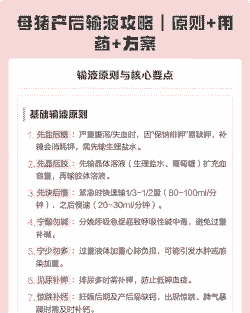

夏季母猪产后输液的方案如下:

第一瓶 :林可霉素30mL + Vc20mL + 缩宫素5IU + 生理盐水500mL。

第二瓶:

鱼腥草30mL + 复合维生素B20mL + 缩宫素5IU + 10%葡萄糖500mL。

对于异常母猪

第一瓶:500mL 生理盐水 + 30mL 黄芪多糖注射液 + 4g 阿莫西林粉 + 半支缩宫素。

第二瓶:500mL 10%葡萄糖溶液 + 20mL 复合维B注射液 + 30mL 10%林可霉素注射液 + 半支缩宫素 + 地塞米松10mg,连用两至三次,直至母猪精神食欲正常。

每头母猪肌注15mL 易针康和15mL 恩诺沙星注射液,分点注射。

建议

消炎与补液并重:

产后输液不仅有助于消炎,还能补充能量和水分,促进母猪恢复。

选择合适的药物:根据母猪的具体情况选择合适的抗生素和补液类型,如林可霉素、鱼腥草、阿莫西林等。

控制输液速度:输液速度应控制在每分钟20 - 30滴,避免过快导致心脏负担过重。

观察反应:在输液过程中要密切观察母猪的反应,如出现异常应及时调整输液速度或停止输液。

保持卫生:确保输液设备和药品的清洁和无菌,减少感染风险。

通过以上方案,可以有效促进夏季母猪的产后恢复,减少疾病的发生。